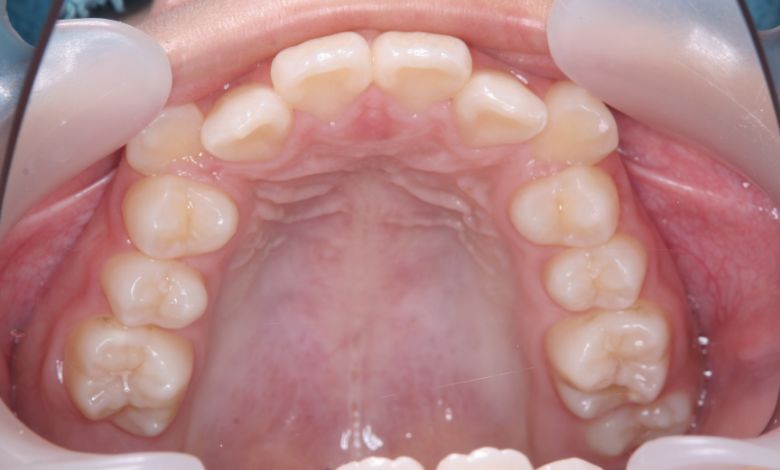

上下顎ともに犬歯が唇側に大きく突出しており、歯列弓が狭小なため、

他院では上下左右4本の便宜抜歯を前提とした矯正治療を提案されていました。

上顎には左右の犬歯が著しく唇側に偏位している

精密検査の結果、当院では抜歯を行わず、歯列弓の拡大によってスペースを確保し、非抜歯での矯正治療を選択しました。歯列の叢生(ガタガタ)は解消され、機能的かつ審美的に優れた咬合が得られました。